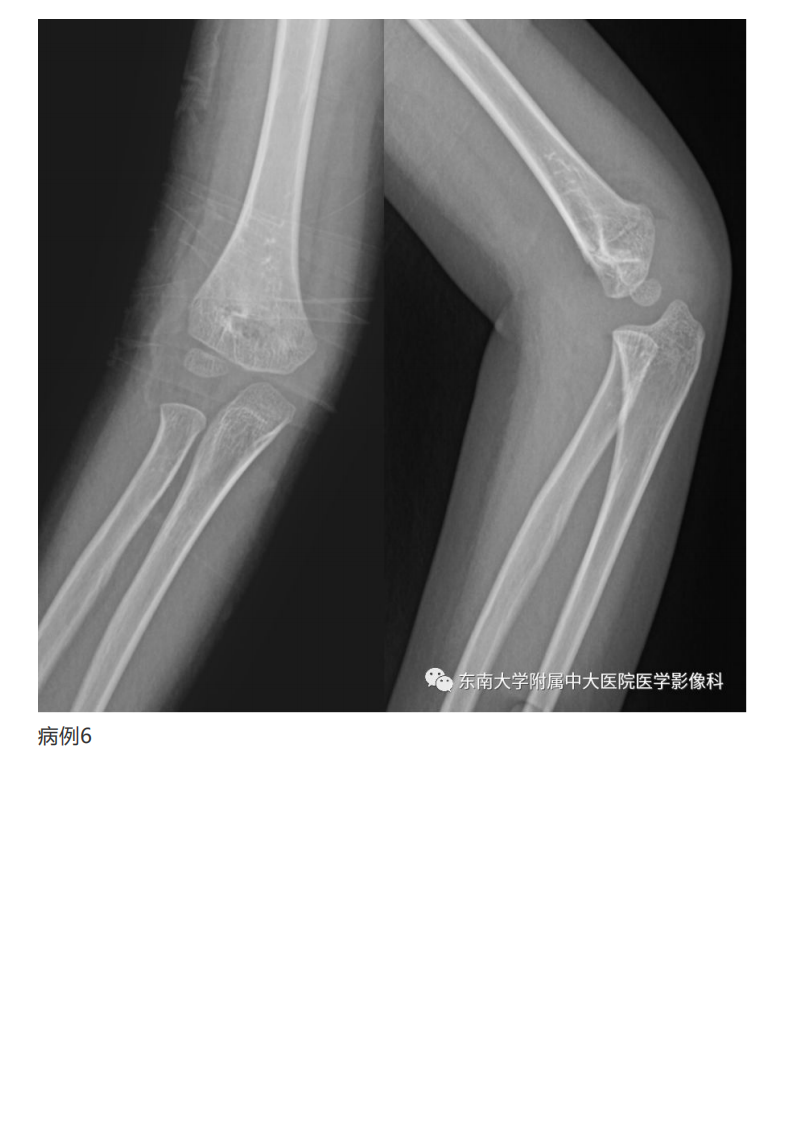

20190409_2【晨读结果公布】2019.04.08肌骨系统疾病.pdf